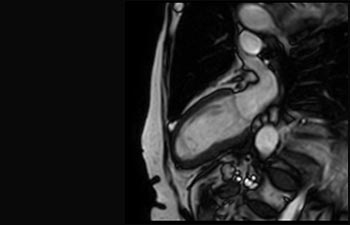

La Sra. Silvia Schiffer, directora y radióloga experta en la clínica Radiologie Schiffer, en Alemania, comparte sus experiencias con el sistema de RM Prodiva 1.5T.

Conozca la opinión de los primeros usuarios de Ingenia Prodiva 1.5T acerca de sus experiencias con el sistema y cómo influye este en su centro de diagnóstico por imagen.